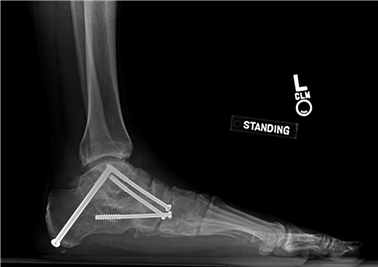

To achieve multiplanar correction, the surgeon must address the sagittal, coronal, and transverse planes. The first metatarsal is plantarflexed to restore the longitudinal arch, rotated out of pronation to realign the sesamoids, and translated laterally to close the IMA. Subchondral drilling or feathering is performed to optimize the biological environment for fusion. Fixation is traditionally achieved with two or three crossed solid or cannulated screws (typically 3.5mm or 4.0mm). Recently, plantar or medial locking plates have gained immense popularity due to their superior biomechanical construct, allowing for earlier weight-bearing. Bone graft or orthobiologics may be packed into the arthrodesis site to stimulate osteogenesis.

Positioning of the fusion is the most critical step of the operation. The hallux must be positioned in 10-15 degrees of valgus, 15-20 degrees of dorsiflexion relative to the first metatarsal, and neutral rotation. Excessive dorsiflexion causes shoe impingement, while insufficient dorsiflexion leads to vaulting during gait and interphalangeal joint arthritis. Fixation is most reliably achieved using a pre-contoured dorsal locking plate combined with a lag screw crossing the fusion interface.

Clinical & Radiographic Imaging Archive